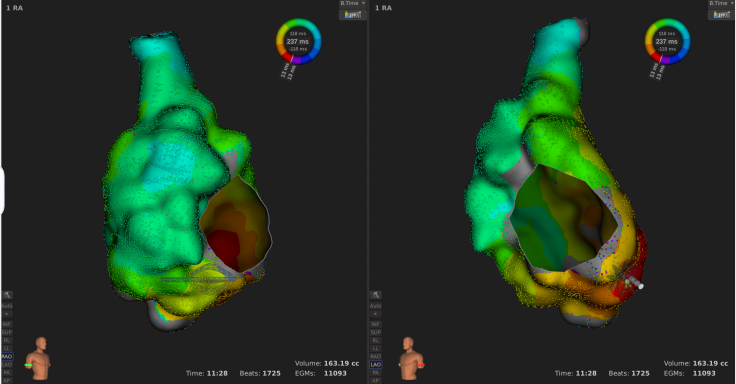

患者上台常规消毒铺巾,心电图显示心房扑动,周长为240ms,穿刺后,先行右房标测,标测结果显示最早激动点由冠状窦口传出,右房整体激动时间占心动过速周长约1/2。遂穿刺房间隔至左房,左房标测结果可见该心动过速绕二尖瓣进行折返,切换电压基质图可见顶部线已断,前壁线区域部分恢复,疤痕部分参与传导。遂先行消融前壁线,以40w 43℃功率模式放电,放电过程中平均单点阻抗下降约25Ω。至前壁线消融结束,心动过速周长延长至260ms. 再行消融二尖瓣峡部线,自瓣环拉至左下肺静脉过程中,DIRECTSENSE™局部阻抗监测技术显示单点阻抗下降约12Ω,心动过速周长逐渐延长至300ms,消融左下肺静脉口蓝点处,心动过速终止。巩固消融后,起博验证,二尖瓣峡线隔离成功。反复burst刺激诱发未见心动过速,本次手术结束。整台手术仅历时90分钟,病人术后感觉良好。

2、右房标测显示窦口最早